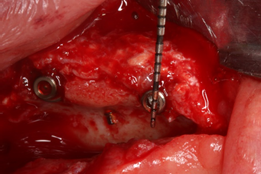

Para a realização da ROG, utilizou-se a técnica Barbell Technique6 (Figura 3), com um enxerto composto por osso autógeno particulado e substituto ósseo mineral inorgânico de origem bovina Bio-Oss (Geistlich) na proporção 1:1, coberto por uma membrana de colágeno reabsorvível Bio-Gide (Geistlich).

O implante Maestro tem se demonstrado como uma excelente opção em pacientes com baixa qualidade óssea, como também em regiões onde foram realizados procedimentos de enxertia óssea. Para a reabilitação desse caso clínico específico, os implantes Maestro Cone Morse e HI foram escolhidos devido às suas características diferenciadas de macrogeometria, aliadas ao seu tratamento de superfície. As câmaras de cicatrização incorporadas na macrogeometria dos implantes Maestro apresentam uma evidente aceleração no processo de osseointegração, bem como na qualidade desse processo 7,8. O design do implante favorece sua inserção com baixo torque, o que é essencial em regiões enxertadas. Os implantes foram instalados com torques de travamento primário variando entre 10 e 25 N (Figuras 5 a 8).